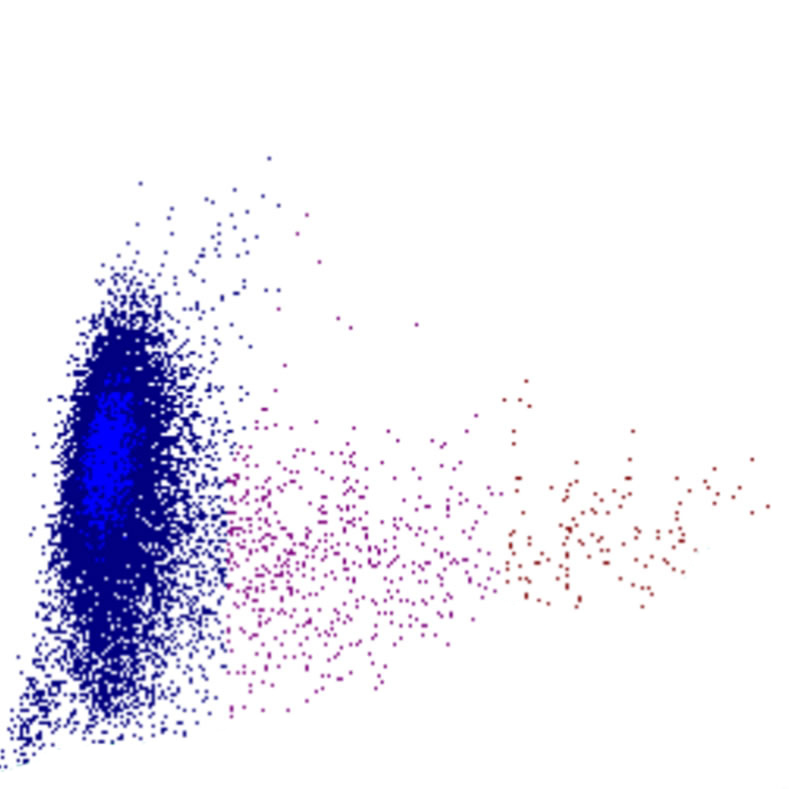

Forward Scatter

Le FSC est une mesure de la taille cellulaire : des valeurs élevées de FSC indiquent des cellules plus grandes, tandis que des valeurs plus faibles correspondent à des cellules plus petites. Les plaquettes présentent le FSC le plus bas, tandis que les monocytes, les lymphocytes plasmocytoïdes et certains blastes figurent parmi les cellules les plus volumineuses.

FSC scatter

FSC faible

FSC élevé